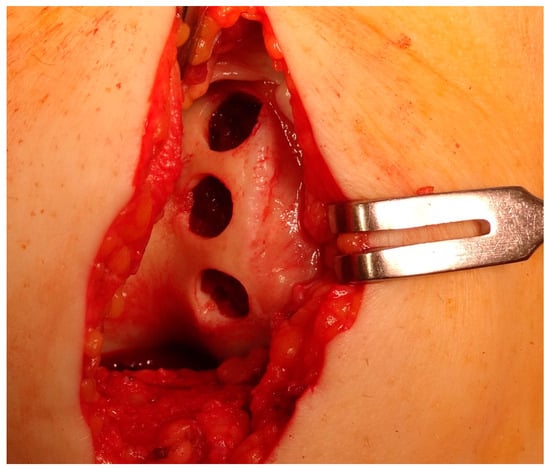

Figure 6.

Arthroscopic view of grade IV lesion with subchondral bone exposure and complete cartilage loss, with only islands of cartilage visible on the medial femoral condyle.